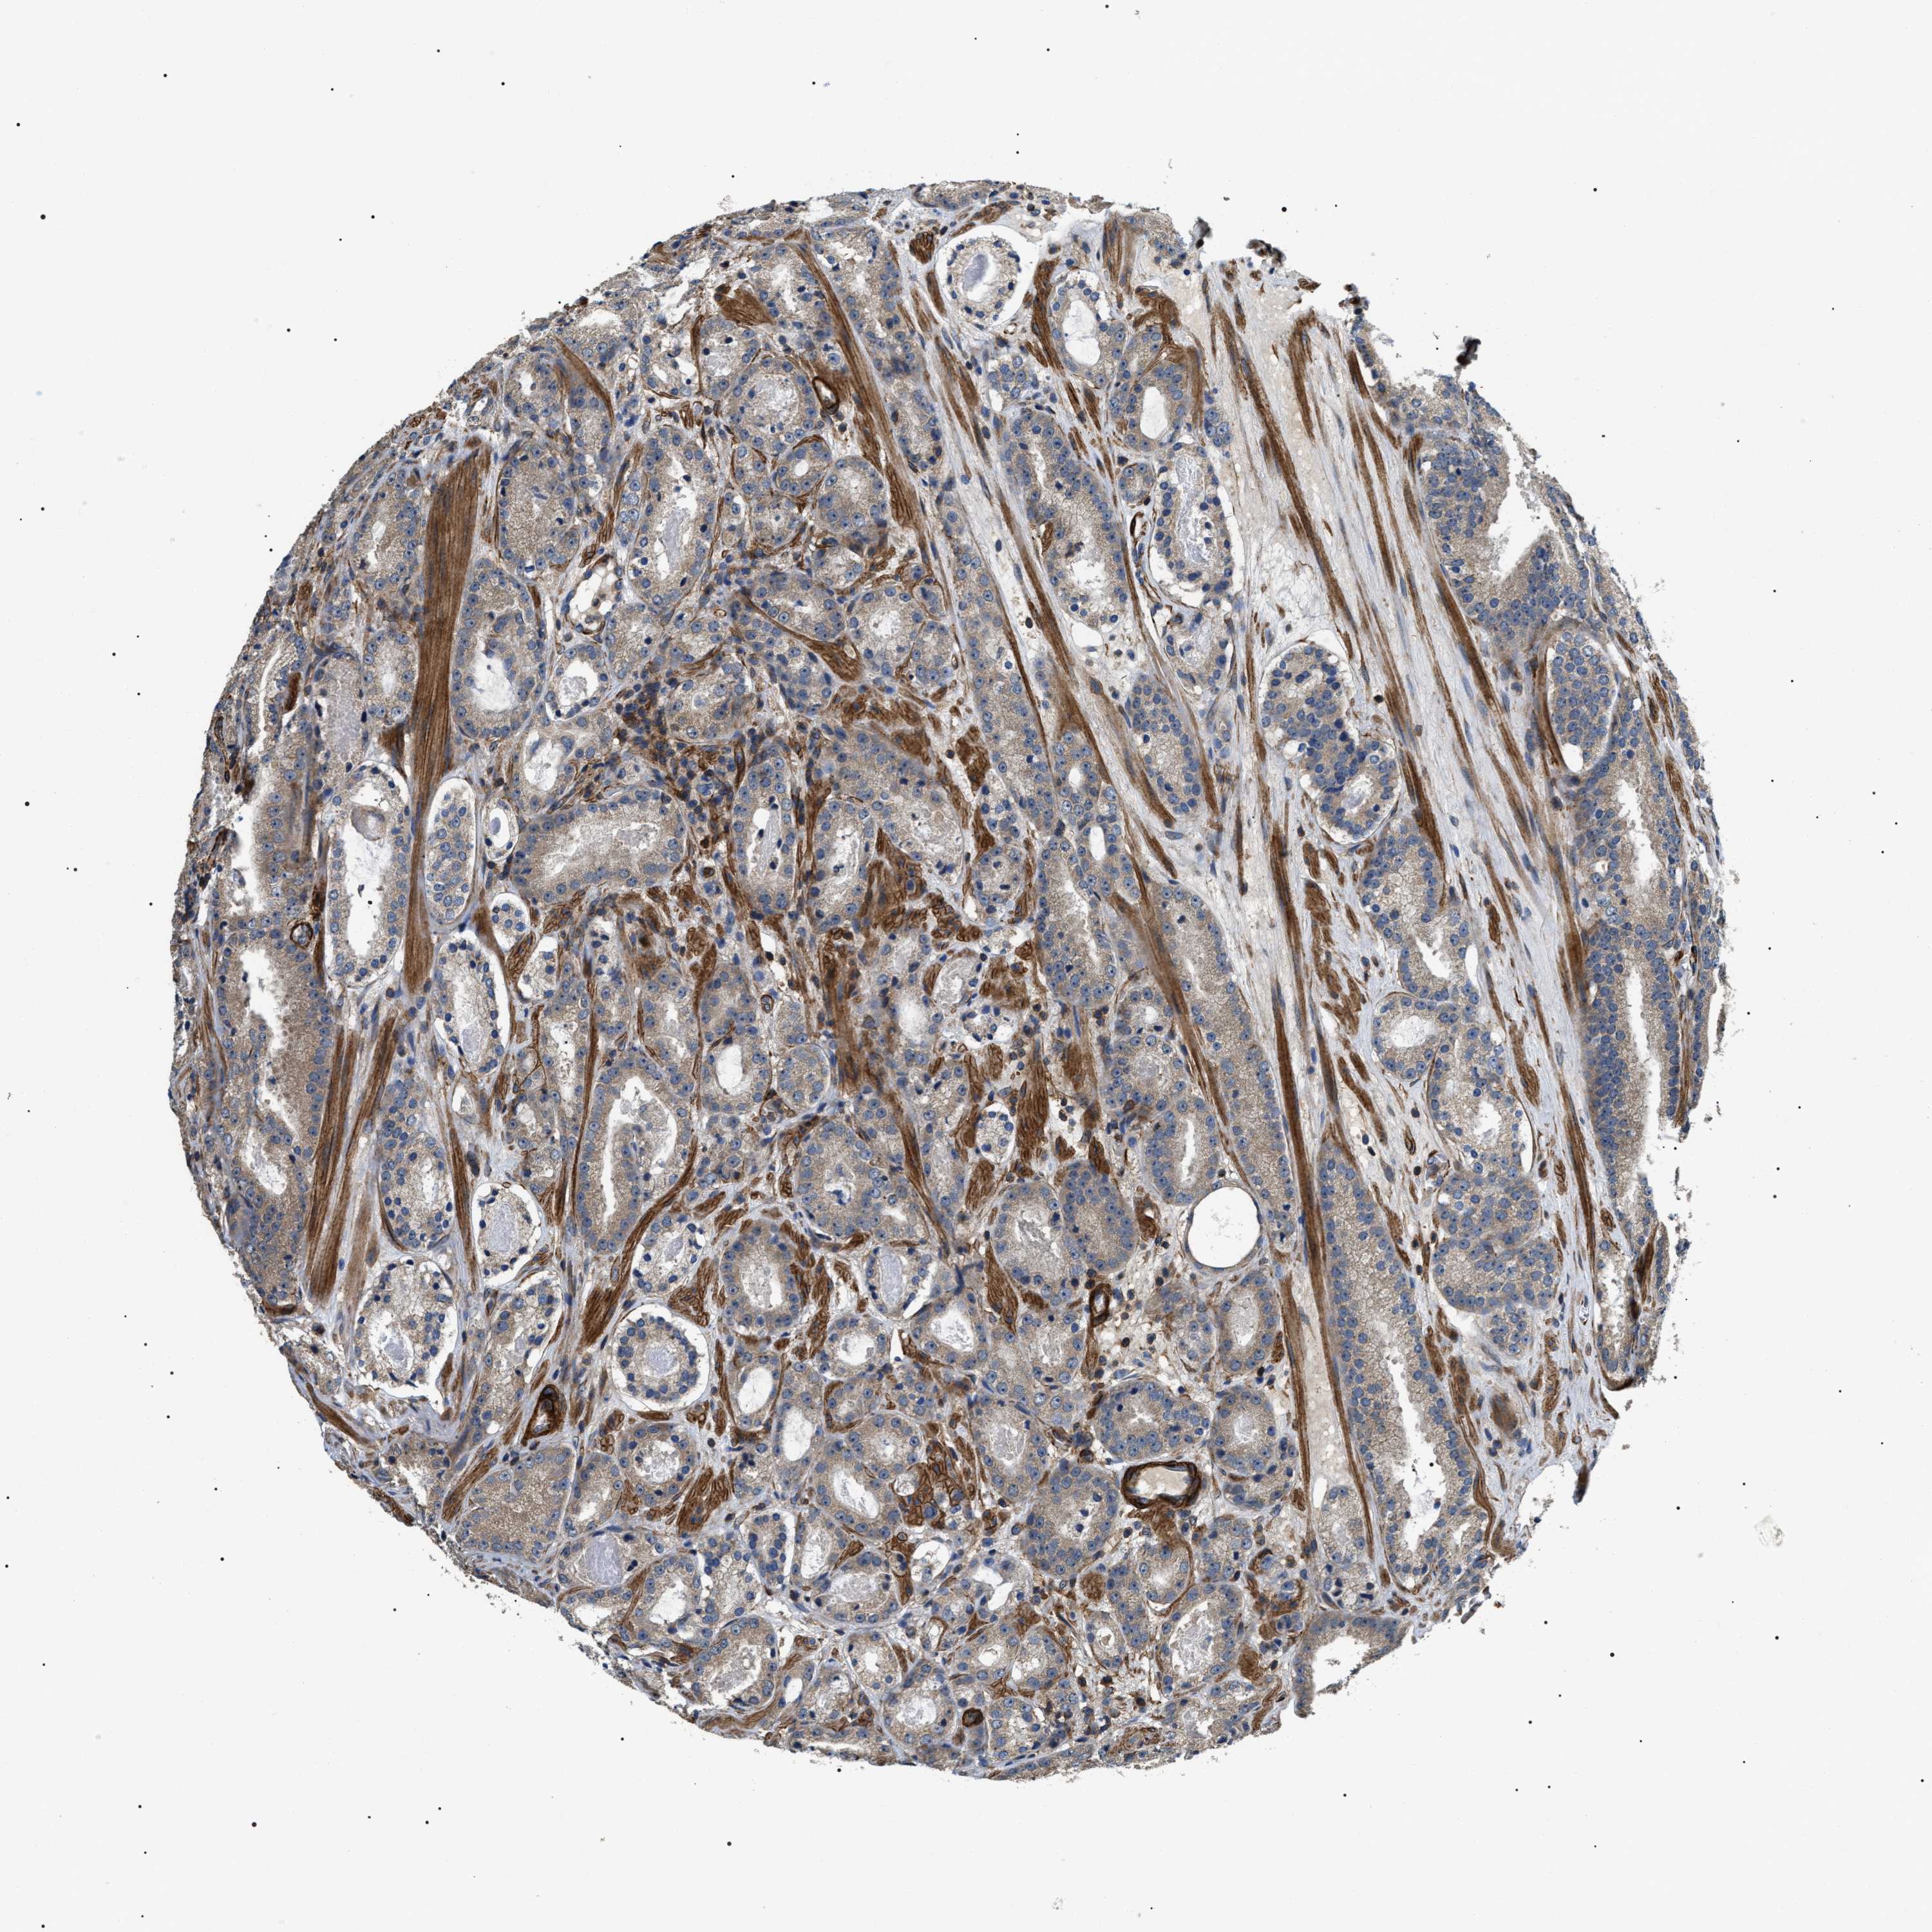

PROSTATE CANCER - Protein expressioni

A mouse-over function shows sample information and annotation data. Click on an image to view it in a full screen mode. Samples can be filtered based on level of antibody staining by selecting one or several of the following categories: high, medium, low and not detected. The assay and annotation is described here.

Note that samples used for immunohistochemistry by the Human Protein Atlas do not correspond to samples in the TCGA dataset.

Antibody stainingi

Antibody staining in the annotated cell types in the current human tissue is reported as not detected, low, medium, or high, based on conventional immunohistochemistry profiling in selected tissues. This score is based on the combination of the staining intensity and fraction of stained cells.

Each image is clickable and will lead to virtual microscopy that enables deeper exploration of all samples and also displays staining intensity scores, fraction scores and subcellular localization as well as patient and tissue information for each sample.

Antibody HPA020386

Staining

High

Medium

Low

Not detected

Intensity

Strong

Moderate

Weak

Negative

Quantity

>75%

75%-25%

<25%

None

Location

Nuclear

Cytoplasmic/membranous

Cytoplasmic/membranous,nuclear

Adenocarcinoma, High grade

Adenocarcinoma, Low grade